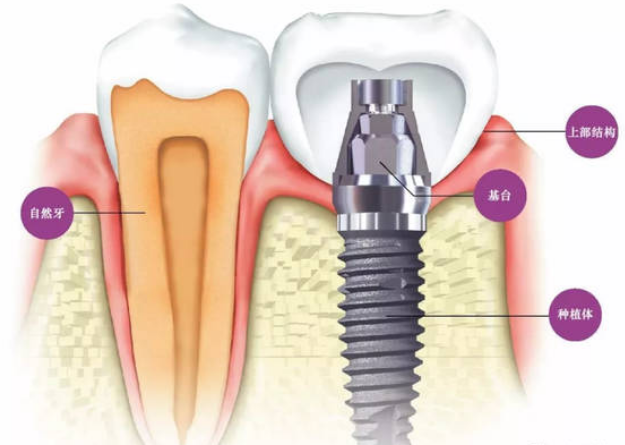

廊坊圣洁口腔医院的医师说,种植牙也叫人工种植牙,并不是真的种上自然牙齿,而是通过医学方式,将与人体骨质兼容性高的纯钛金属经过精密的设计,制造成类似牙根的圆柱体或其他形状,以外科小手术的方式植入缺牙区的牙槽骨内,经过1~3个月后,当人工牙根与牙槽骨密合后,再在人工牙根上制作烤瓷牙冠。 》》》相关阅读:廊坊市民种植牙成功的四要素

优点:种植牙依靠种植体本身与牙槽骨的骨结合固位,它的修复不需要损伤相邻牙齿,也不受口腔内余留牙数量的影响,缺一颗牙、缺失多颗牙甚至全口牙缺失,都能进行人工种植。并且,在美观性、功能性、稳固性、舒适性上都具有接近真牙的功能。